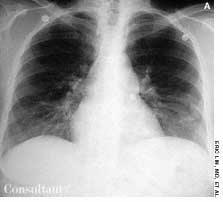

A 97-year-old woman with a history of hypertension and a paraesophageal hiatal hernia presented with abdominal distention and shortness of breath. Three days earlier, she had fallen and sustained a hairline pelvic fracture; she was evaluated in the emergency department and given narcotics for the pain. Subsequently, the patient's abdomen became increasingly distended, and she had no bowel movement for 3 days.